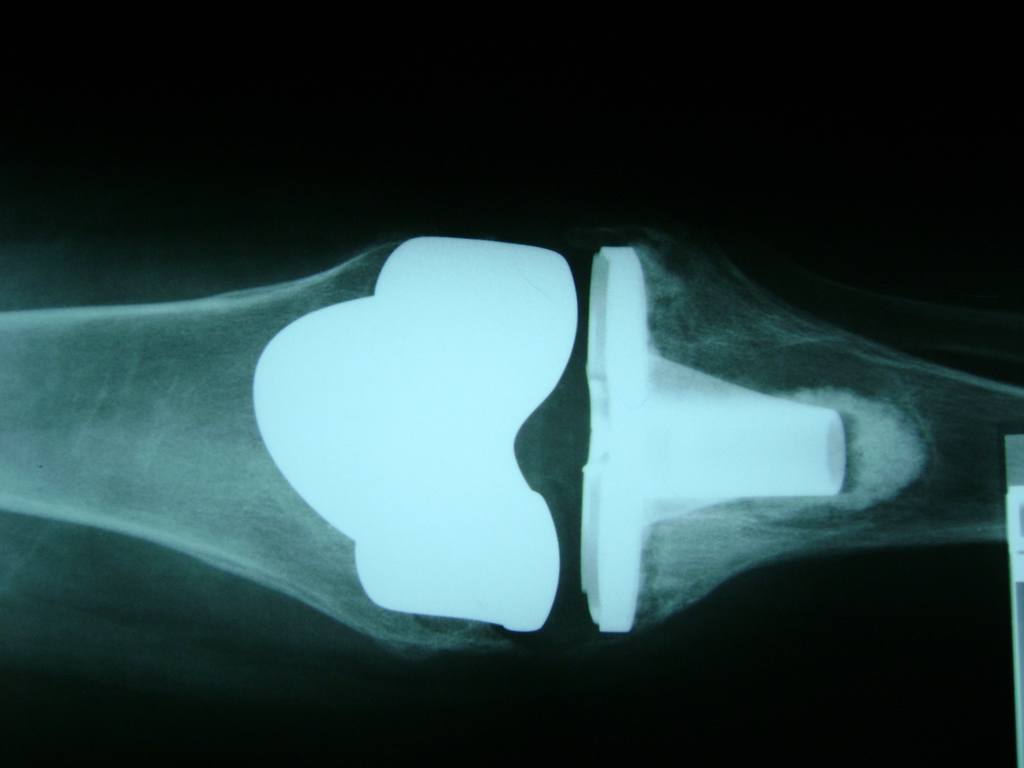

La artroscopia de rodilla es un cirugía en el cual la estructura interna de la articulación es examinada ya sea para realizar un diagnostico o para realizar un tratamiento, este procedimiento se realiza utilizando un instrumento parecido a un pequeño tubo llamado artroscopio.